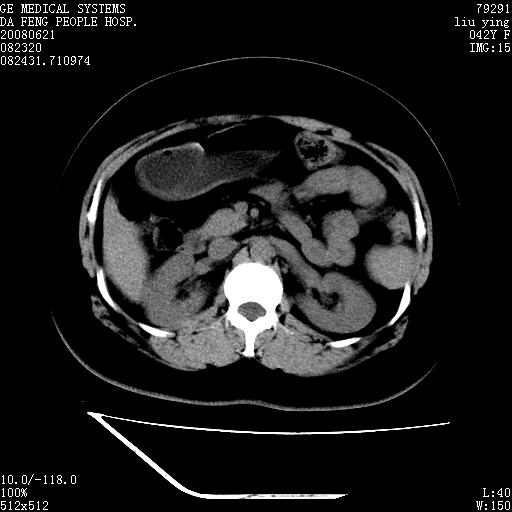

标题: CT14225:女性46岁。当地B超示肝内占位,来我院作CT检查。请 [打印本页]

标题: CT14225:女性46岁。当地B超示肝内占位,来我院作CT检查。请

速升速降,支持肝癌.脾体积增大,形态欠规整,请询问病史是否做过脾动脉栓塞.

速升速降,支持肝癌可能。

右叶肝癌灶;慢性胆囊炎,不除外占位;;副脾可能性

快进快出,符合肝癌表现-----------

肝内结节强化特点符合原发性肝癌表现,脾脏改变考虑为增大及先天发育所致。

动脉期病原灶明显强化高于肝密度且中央有无强化区,静脉期强化程度下降明显,延迟低于肝密度,考虑肝腺瘤可能性大,

肝内结节强化特点:快进快出符合原发性肝癌表现

此患者虽然符合快进的特点,却不符合快出的特点,因为门脉期几乎是等密度,不符合肝癌的增强表现,所以我考虑肝局灶性结节增生可能性大